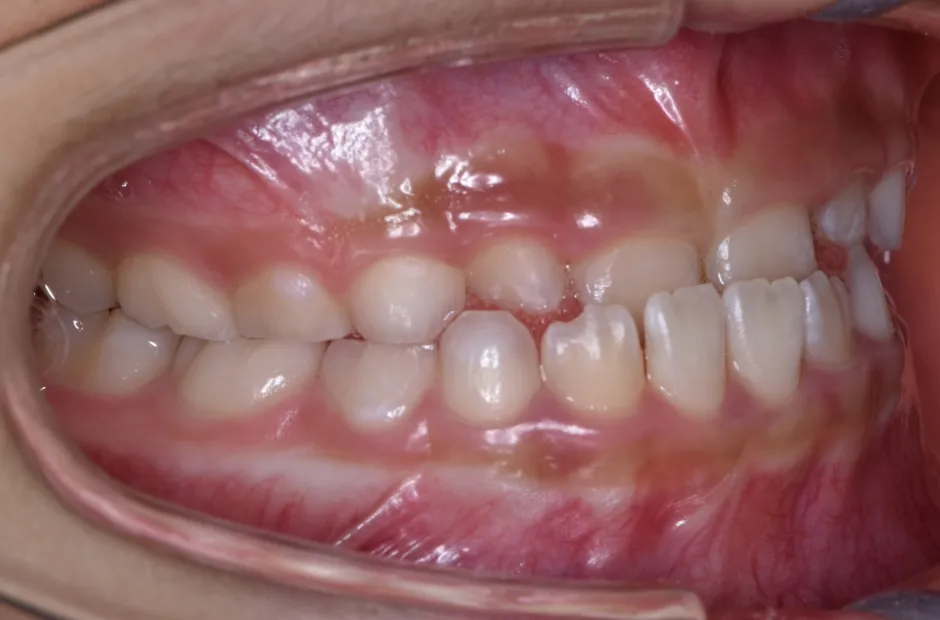

叢生

| 診断名・主訴 | 叢生 |

|---|---|

| 年齢・性別 | 10歳・女性 |

| 治療期間・回数 | 2年半 |

| 治療に用いた主な装置 | 拡大床装置 |

| 抜歯部位 | なし |

| 治療費 | 30万円(税抜) |

| リスク・副作用 | 装置による違和感・疼痛・歯肉退縮・歯根吸収・虫歯のリスクなど |

治療前

治療中

治療後